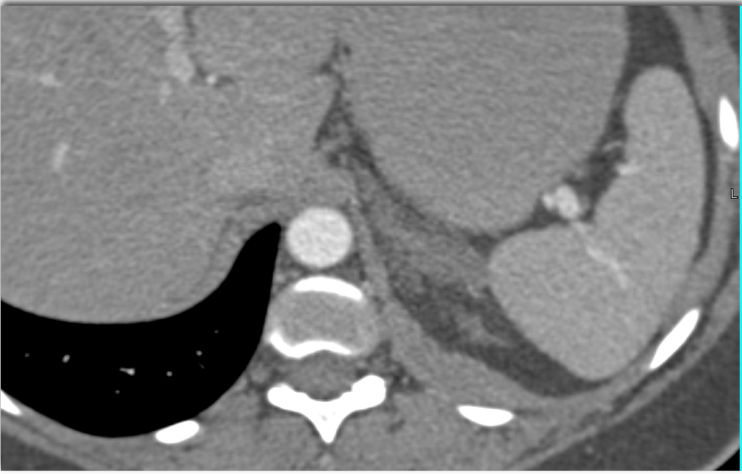

8) In this patient with acute back pain the best diagnosis is?

lymphoma

adrenal hemorrhage due to coumadin

adrenal hyperplasia

adrenal infection like TB